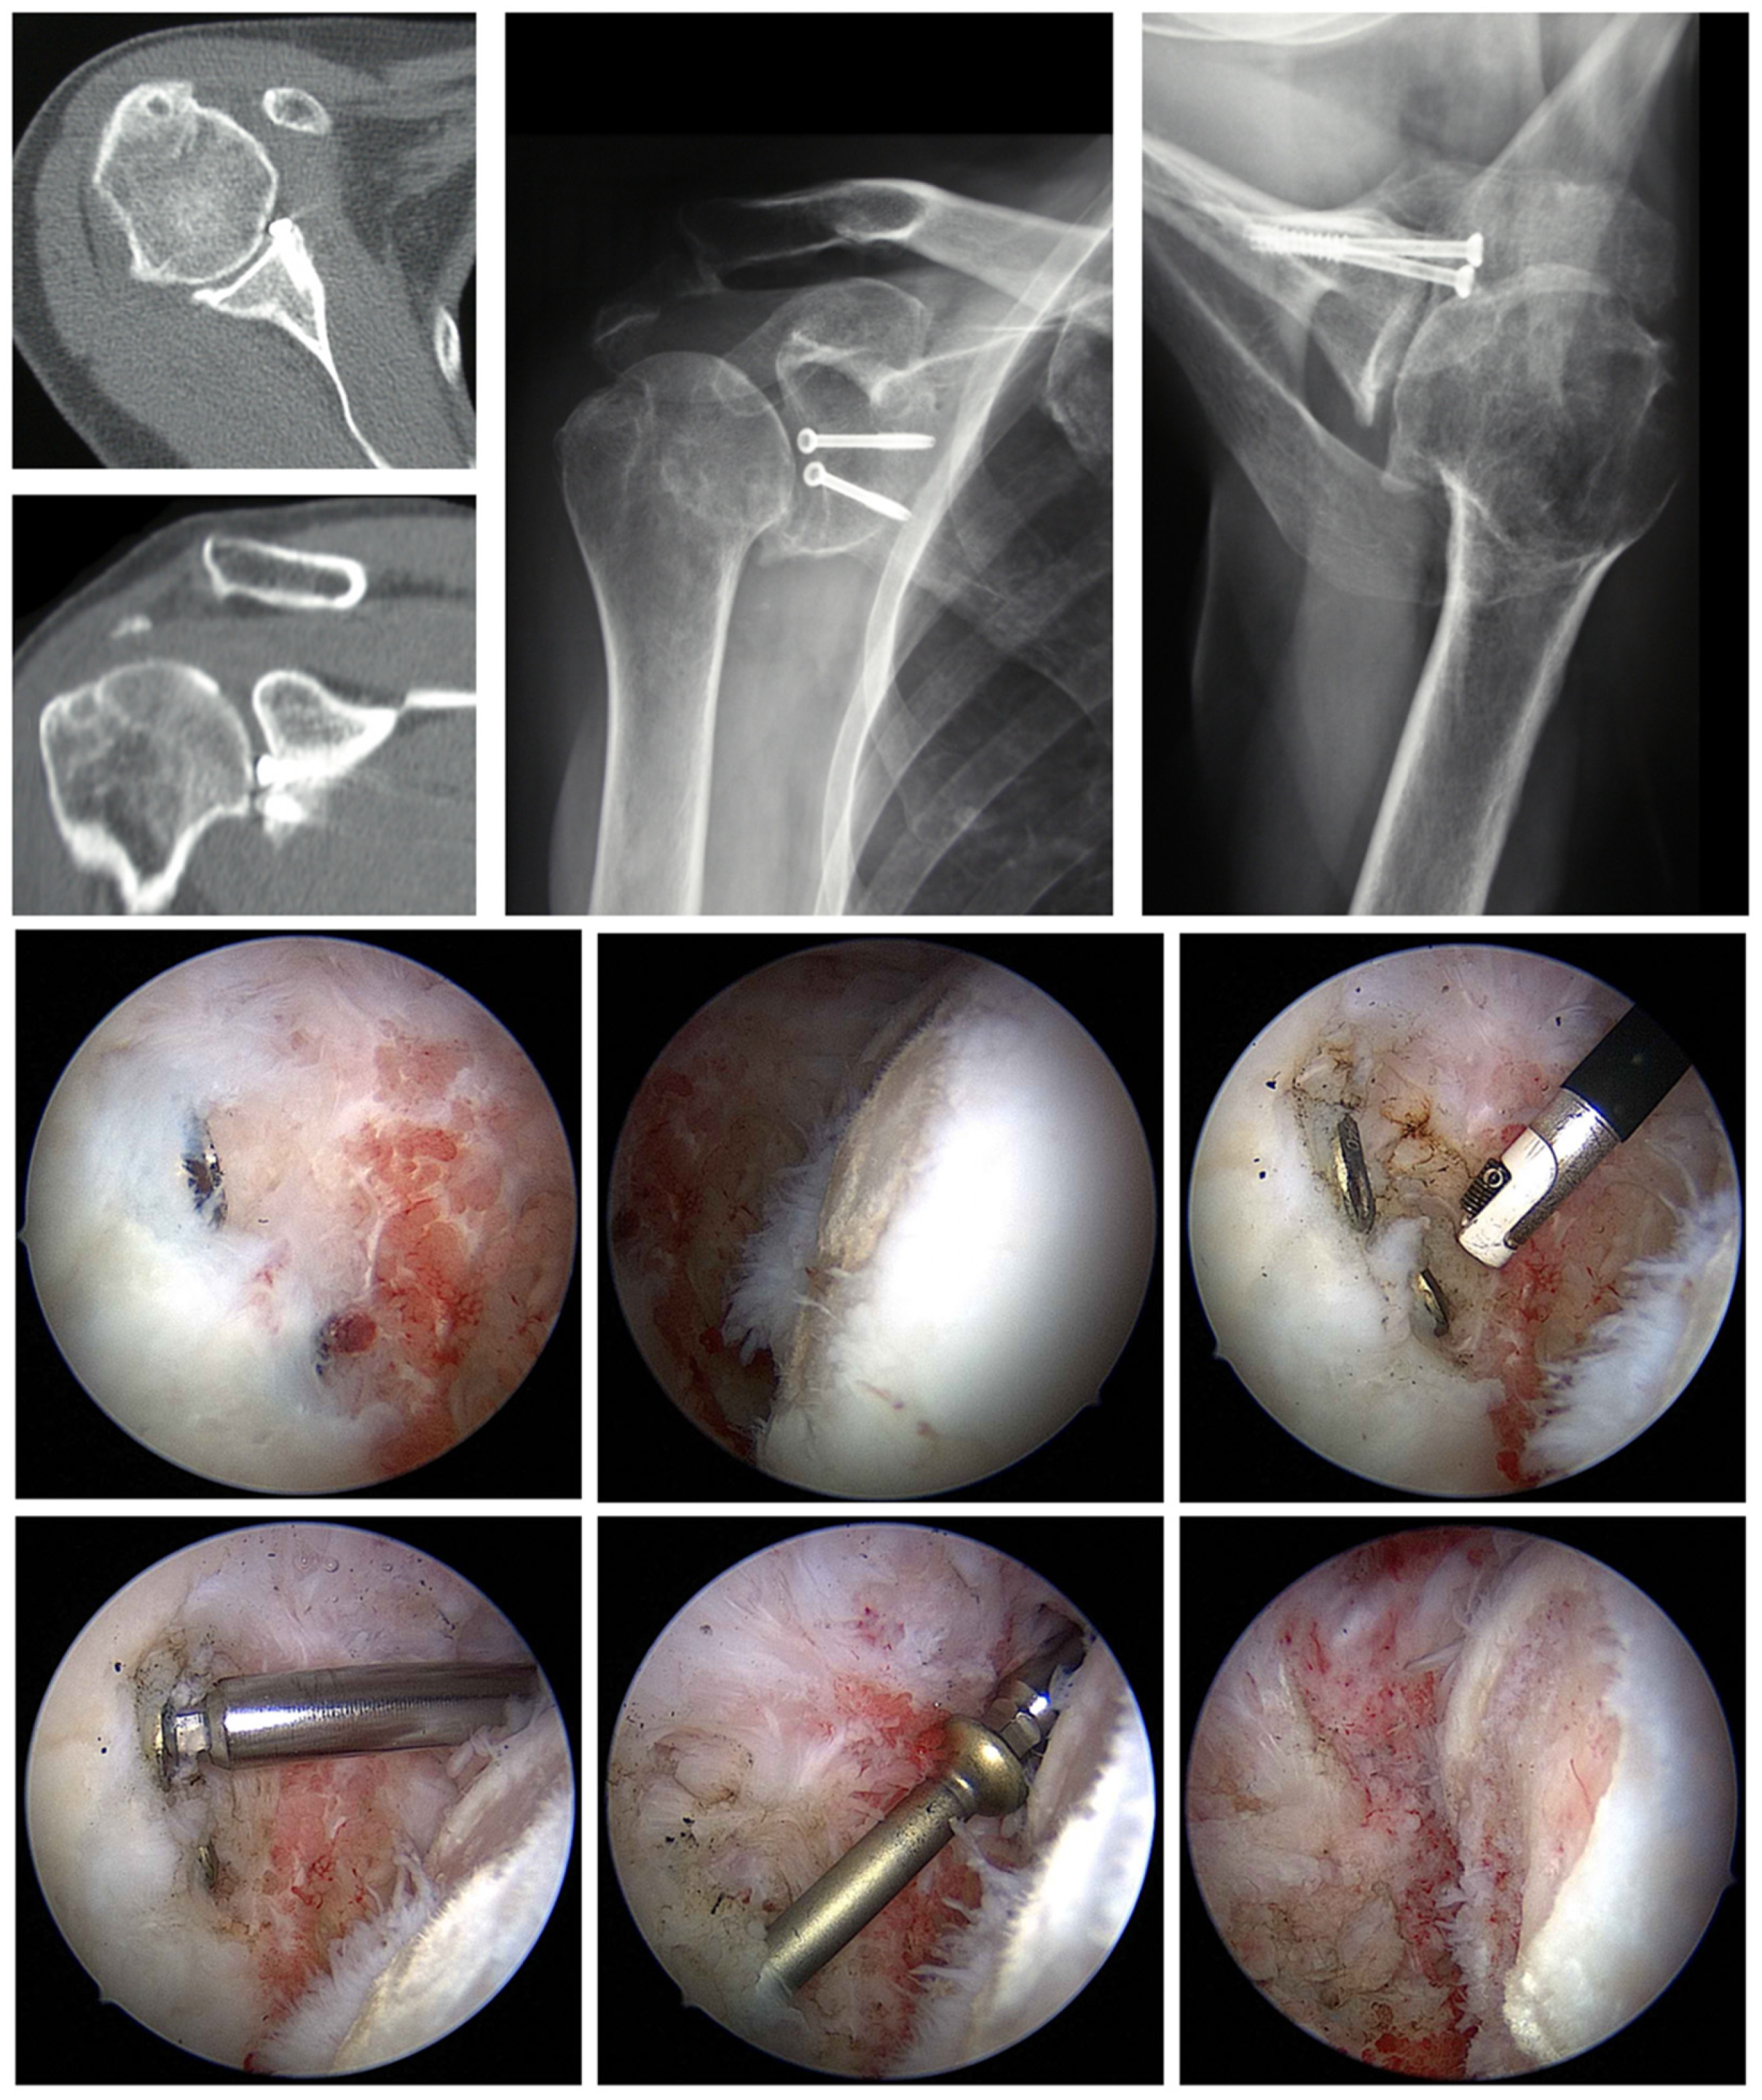

6.2. Removal of Foreign Material

6.3. Arthroscopic Debridement and Arthrolysis

- Tauber, M.; Moursy, M.; Eppel, M.; Koller, H.; Resch, H. Arthroscopic Screw Fixation of Large Anterior Glenoid Fractures. Knee Surg. Sports Traumatol. Arthrosc. 2008, 16, 326–332. [Google Scholar] [CrossRef]